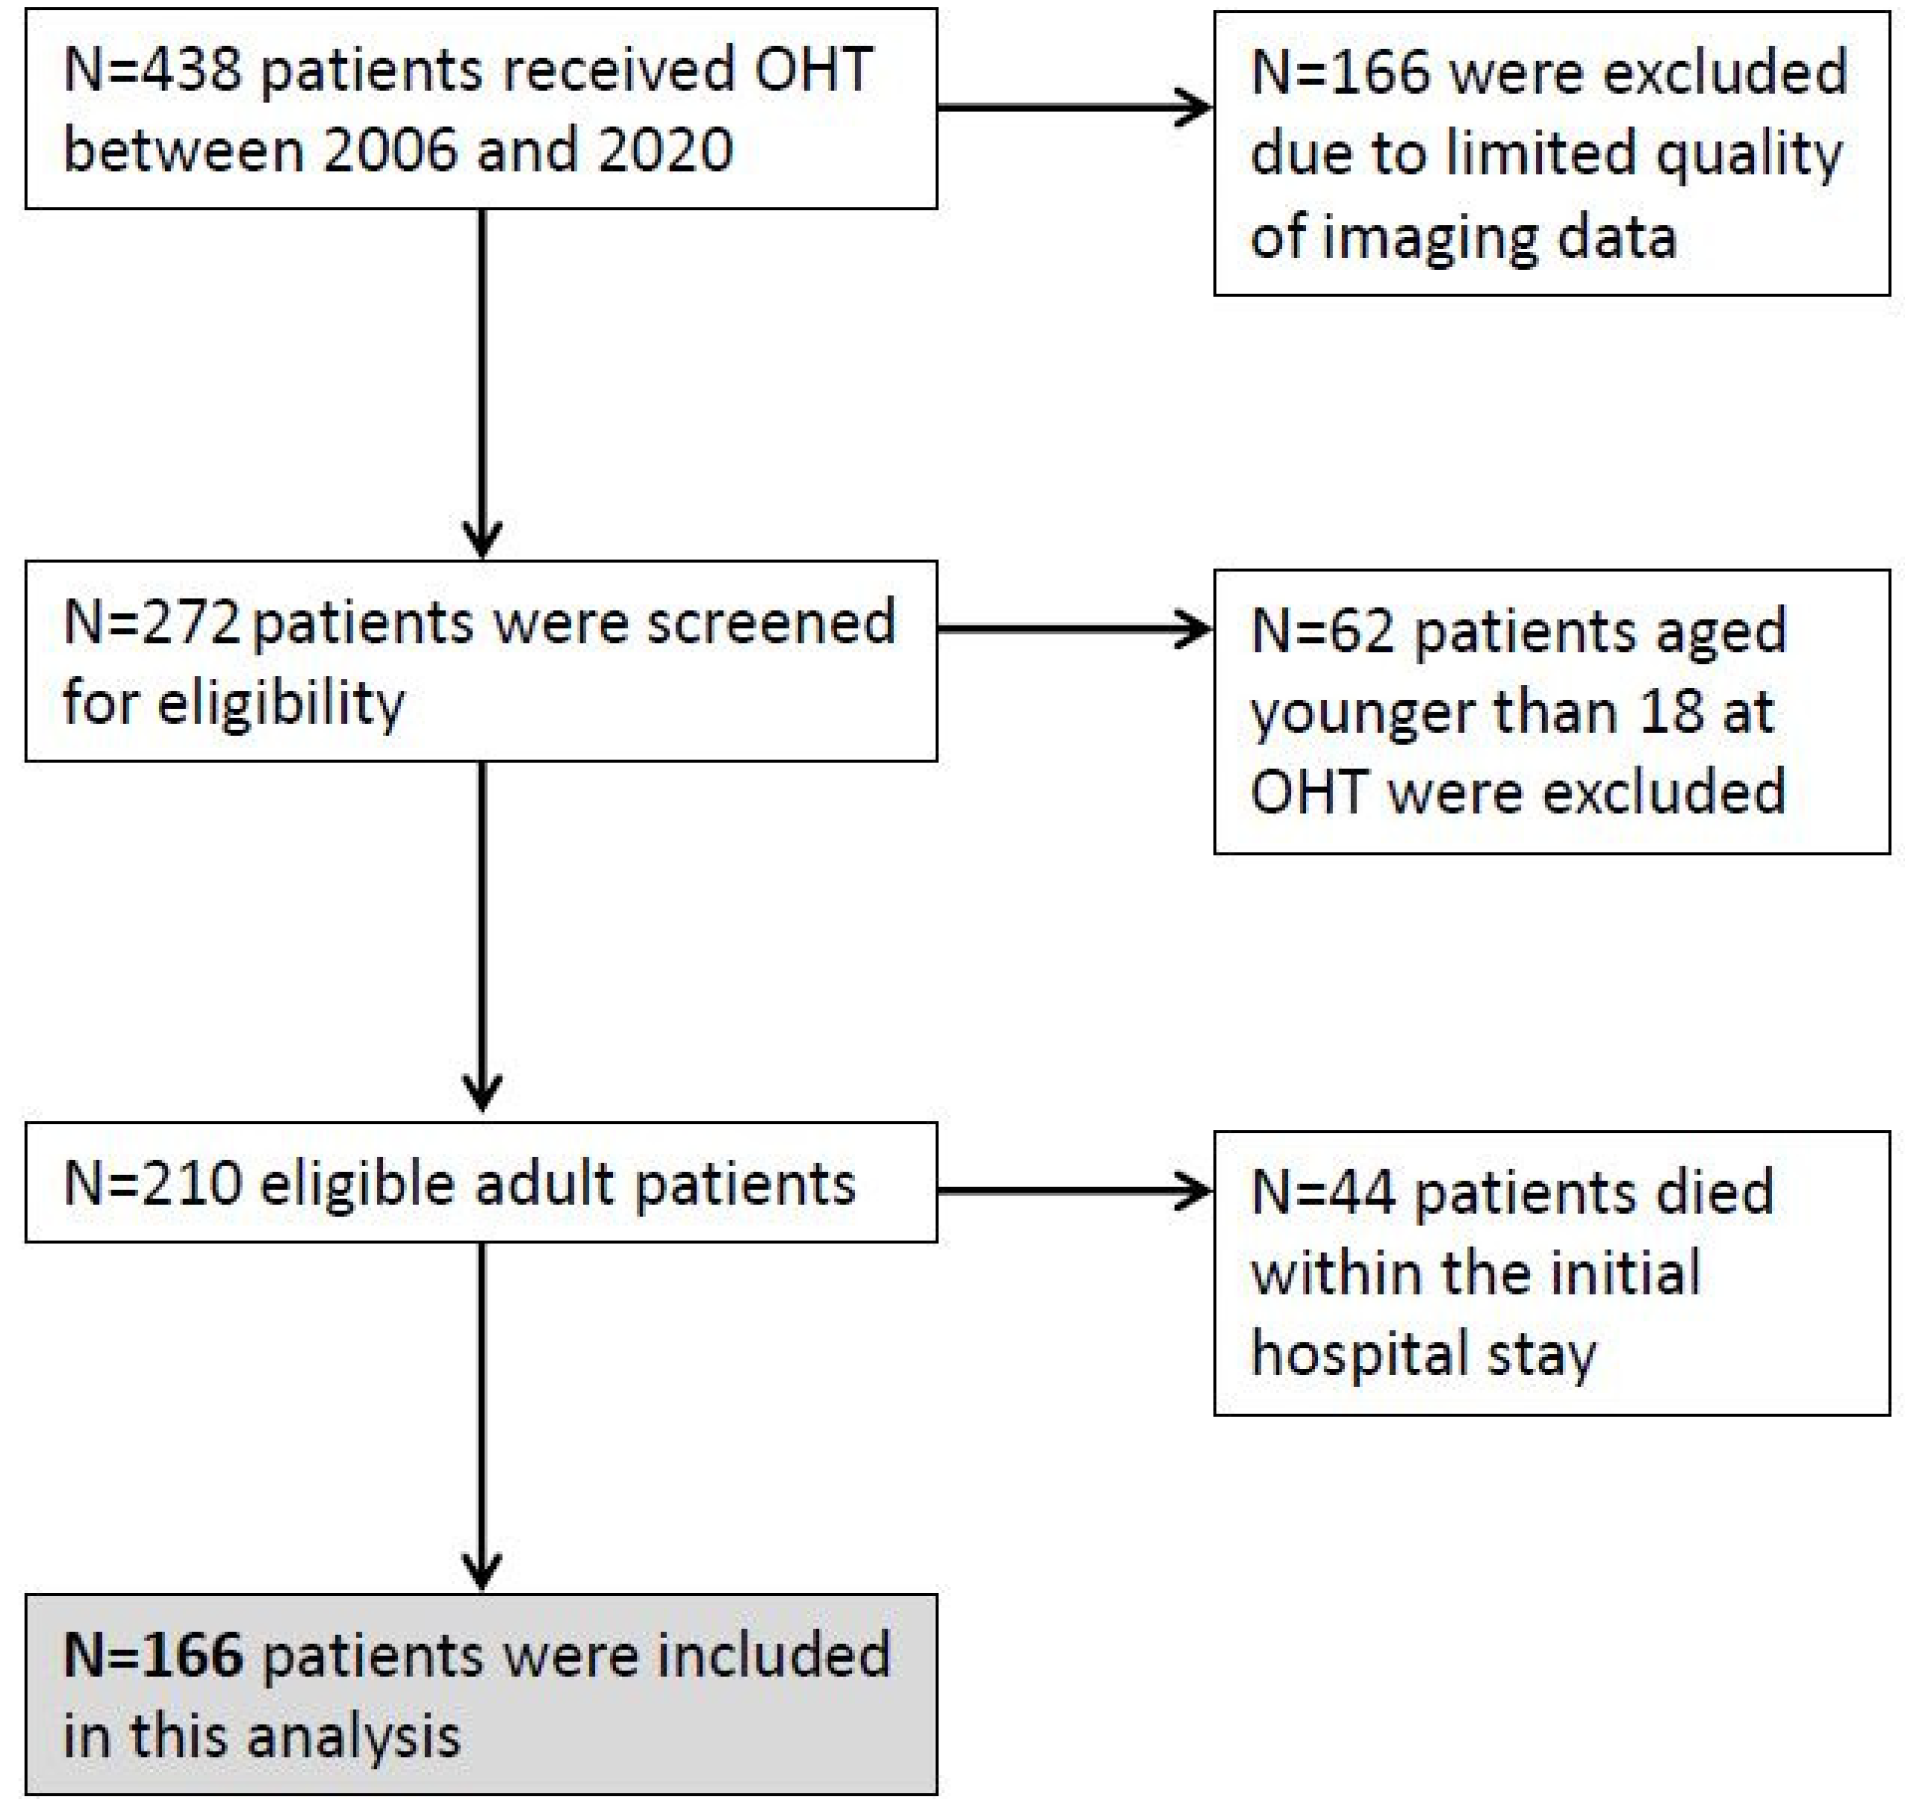

2. Materials and Methods

3.1. Patient Characteristics